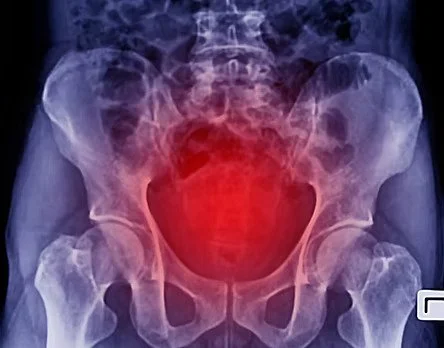

The physical definition of a neutral pelvis is when your pubic synthesis, (commonly referred to as pubic bone) is on the same plane as your anterior iliums (the bones you feel when placing your hands on your hips). In standing line with gravity, the “sit bones” or ischiums reach directly downward and the very top of the iliums are level to ceiling.

In this neutral position, when we learn how to apply it to various movement directions, we can safely load the spine i.e. lift something with significant weight, because our natural spinal curves can best absorb the shock of the weight. You will see this in medical advice for bending from the knees and hips instead of the spine.

Many of us don’t know what it feels like to keep the pelvis neutral. It is possible to both over tuck and under tuck the tail bone. We hear the words “natural lumbar curve” and end up not correcting our anterior tilt, compressing our lower back. There needs to be some amount of naturally occurring muscle engagement throughout the sacral/coccygeal curve, as well as our lower abdominal and pelvic floor to allow the lumbar spine a healthy oppositional lumbar curve. This micro movement around our tail, sacrum, lower abs, and pelvic floor is an essential fundament with many benefits to the entire body, but it needs to come from the front lower abdominal muscles as well.